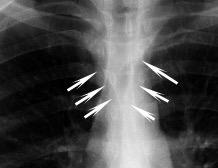

Triada de Garland

Ganglios paratraqueales derechos e hiliares bilaterales

95% de pacientes tienen ganglios hiliares bilaterales aislados o con afectación mediastínica (espec. paratraqueal derecho).

Criado E et al. Pulmonary sarcoidosis: typical and atypical manifestations at high-resolution CT with pathologic correlation. Radiographics. 2010